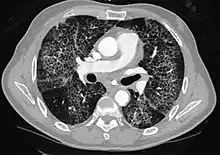

- Influenza CT image showing ground-glass opacification in the posterior of the right lung (screen left). CT image showing ground-glass opacification in the posterior of the right lung (screen left).

- Lung adenocarcinoma.jpg.webp) CT image showing diffuse GGOs throughout both lungs. An abscess is also noted in the right lung (screen left). CT image showing diffuse GGOs throughout both lungs. An abscess is also noted in the right lung (screen left).